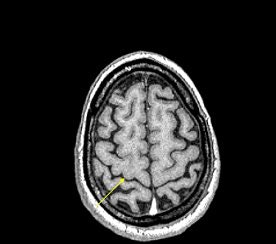

The beauty of SWI in these patients is its ability to image indirectly vessels that are a fraction of a voxel in size. Haacke showed an image acquired on a 3-tesla unit with an in-plane resolution of 0.5 mm x 0.5 mm with a 1-mm slice thickness. Haacke has recently used SWI on a 4-tesla system to see the small veins of the medial venous drainage system (see below).

| SWI data on a 4-tesla unit. In-plane resolution 0.5 mm x 0.5 mm projected over 18 slices of 1-mm slice thickness. Data acquired with a TE = 15 msec. More vessels could be shown if a longer TE had been used, such as 30 msec. This data was collected at Wayne State University in Detroit on a Bruker-Siemens 4-tesla unit. |